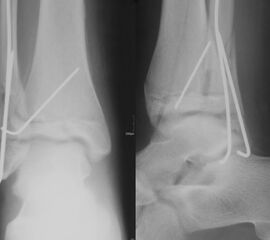

THERAPIE

Behandlungsziel ist die exakte Rekonstruktion der Gelenkfläche sowie die Minimierung des Risikos einer späteren Wachstumsstörung. Dislozierte Frakturen werden offen reponiert, die Osteosynthese erfolgt mit einer Kleinfragmentschraube. Finden sich viele kleine Fragmente kann eine K-Draht Osteosynthese durchgeführt werden. Wird der Innenknöchel operiert, kann bei gleichzeitiger hochgradiger lateraler Instabilität eine Rekonstruktion des lateralen Bandapparats durchgeführt werden. Fibula Frakturen stellen sich meist spontan ein, sodass hier keine zusätzliche Osteosynthese notwendig ist.

Nach der Osteosynthese wird die Fraktur für ca. vier Wochen in einem Unterschenkelgips ruhiggestellt. Bei Schmerzfreiheit der Frakturzone erfolgt anschließend eine schmerzadaptierte Belastungssteigerung über weitere zwei Wochen. Sobald unter Alltagsbedingungen Beschwerdefreiheit besteht kann die sportliche Belastung langsam gesteigert werden. Kirschnerdrähte werden 6-8 Wochen postoperativ, Schrauben nach zwölf Wochen entfernt. Es empfiehlt sich klinische und radiologische Kontrollen im Abstand von 6 Monaten bis zum Wachstumsabschluss durchzuführen, um ein mögliches Fehlwachstum frühzeitig zu erkennen.